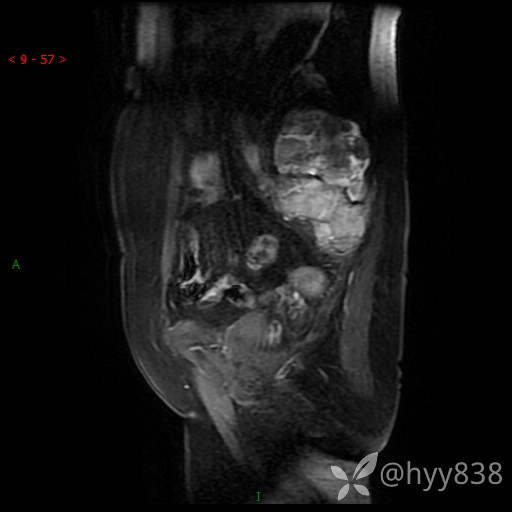

骨盆MRI平扫(T1WI+T2WI+DWI)(外院CT,不能上传)